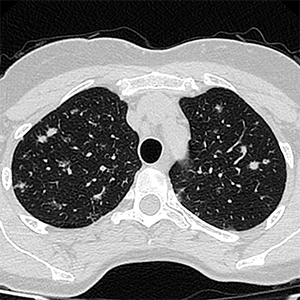

Octubre 2025. Conci Carpinella

Femenina 59 años. Asintomática, Hallazgo en control anual.